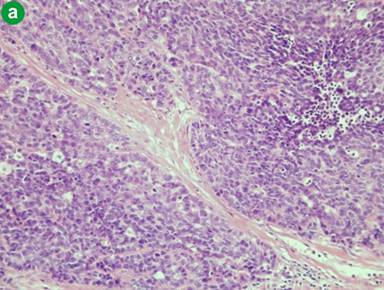

An inclusive narrative review methodology was undertaken. In addition, we briefly review the diagnostic modalities used and the treatment decisions made in the case which presented to our institution. Electronic literature searches were conducted using MEDLINE (PubMed) from 1 January 2000 to 31 August 2011. All English case reports of LCNECs of the ampulla of Vater were selected. The selected search terms and related MESH headings were: “large”, “neuroendocrine” and “ampulla”. In each of the cases selected, the diagnostic criteria for LCNEC of the lung proposed by Travis et al. [12] were satisfied. According to these criteria, tumours are described as having cells at least three times larger than cells of a small cell carcinoma, neuroendocrine morphology (organoid growth pattern, cellular palisading, rosette formation) and an irregular chromatin pattern with brisk mitotic activity [13] (Figure 2a). These criteria were updated in the 1999 WHO classification [14], which added additional criteria including a high mitotic rate of greater than 11 mitoses (when 10 high-power fields of 2 mm2 were examined), extensive necrosis and immunohistochemical evidence of neuroendocrine differentiation. The selected cases also fulfill these additional criteria with all LCNECs in our series immunostaining positive for neuroendocrine markers (Figure 2b). The primary outcome of interest was to determine the overall survival in this rare patient group. The secondary outcome was to determine if having an adenoma in association with a LCNEC improves prognosis.

Figure 2. a. On high power magnification, the neoplastic cells are arranged in well defined solid nest and rosettes with oval vesicular nuclei containing occasional prominent nucleoli. Areas of necrosis are present. b. Tumour cells show strong immunohistochemical detection for synaptophysin. c. Large cell neuroendocrine carcinoma of the ampulla of Vater (top left of field), which is adjacent to a residual villous adenoma of the ampulla with low grade dysplasia (bottom of field). d. Regional lymph node metastasis. Magnifications: 200x, 200x, 20x, and 200x for a., b., c., and d., respectively). |